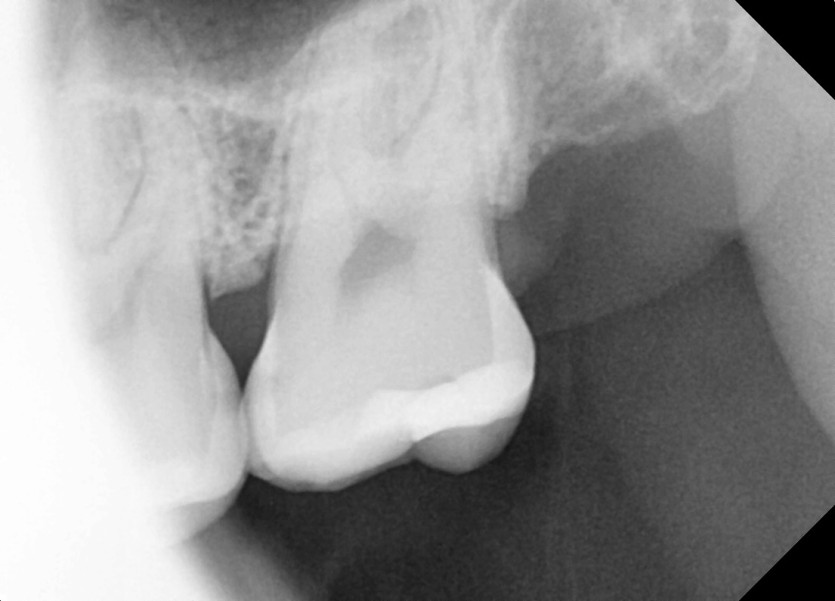

#28,38,48 사랑니 발치

구강 외과 전문의가 당일 발치했습니다.